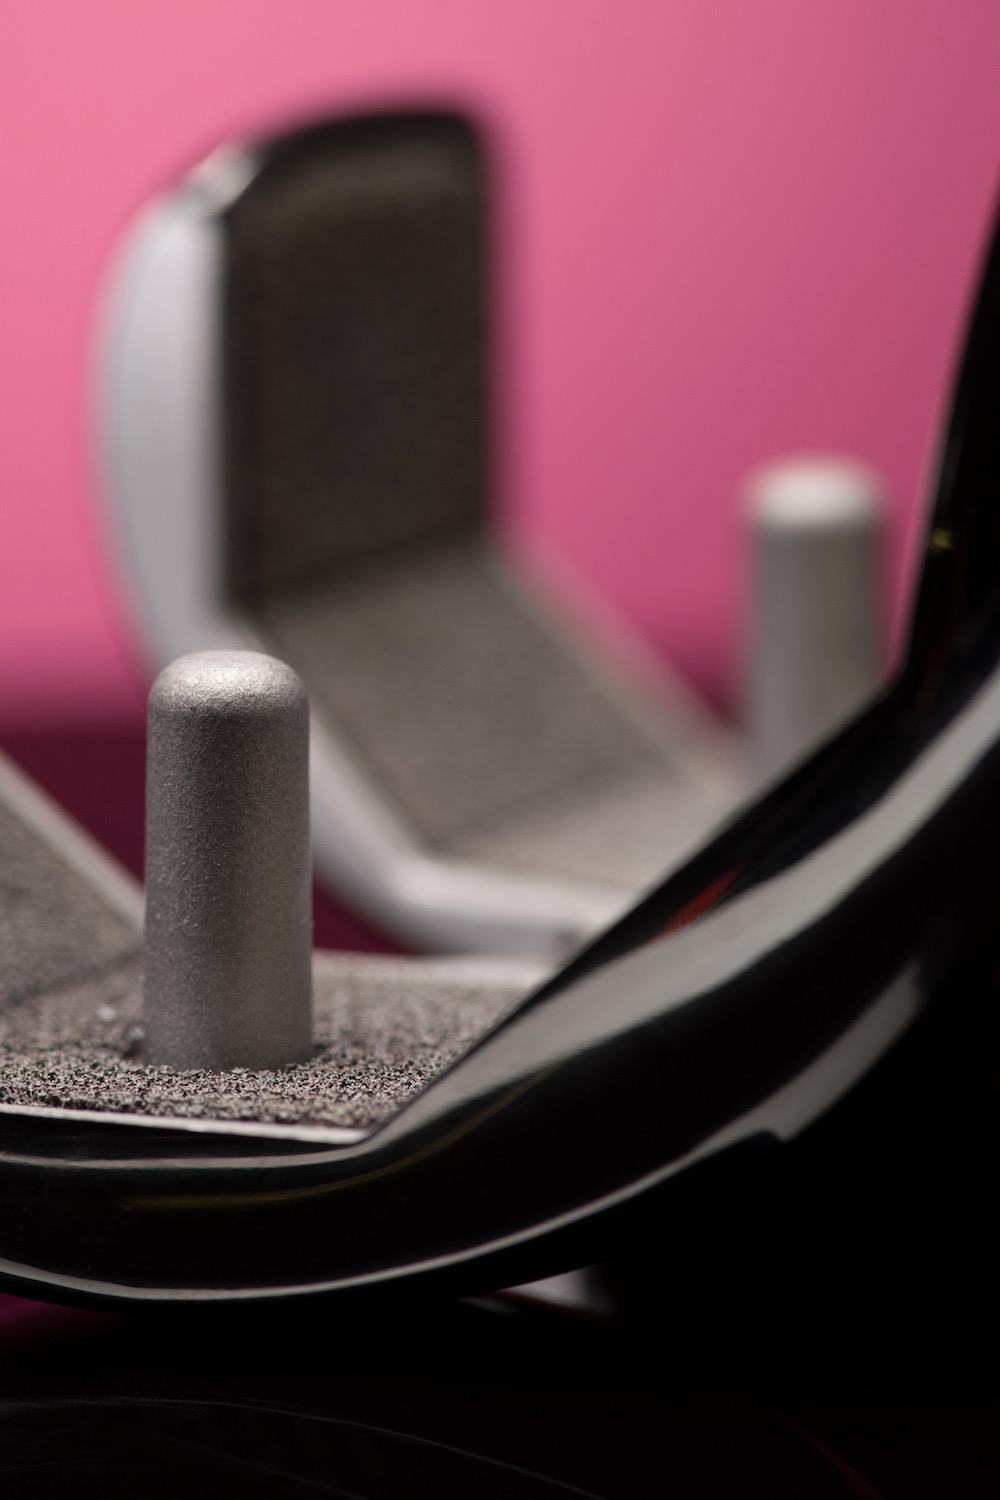

Bei der anatomischem Schulterprothese wird die Gelenkfläche des Oberarmkopfs sowie der Gelenkpfanne ersetzt. Voraussetzung ist eine intakte Muskel- und Sehnenfunktion (Rotatorenmanschette). Mehr erfahren »>

Bei der inversen Prothese tauschen Kugel und Pfanne gleichsam die Position (invers), indem man eine Halbkugel auf der Seite der ursprünglichen Gelenkpfanne montiert und die Pfanne entsprechend auf der Seite des Oberarmkopfes. Mehr erfahren »>